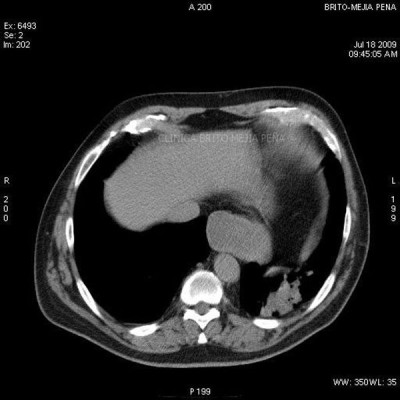

Pseudoquiste páncreas axial